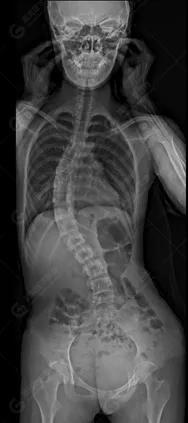

15歲女性,發(fā)現(xiàn)特發(fā)性脊柱側(cè)彎3年,于2019年1月23日來(lái)到廣東高尚醫(yī)學(xué)影像診斷中心行EOS檢查,2019年2月行手術(shù)治療后多次到中心行EOS復(fù)查。

2019-07-04

脊柱側(cè)彎最重要一個(gè)臨床參數(shù)是側(cè)彎角(Cobb角),目前臨床公認(rèn)的Cobb角>10 °診斷為脊柱側(cè)彎;如Cobb角進(jìn)行性持續(xù)性增加>40 °需要手術(shù)矯正治療。

本例患者胸椎右側(cè)彎,Cobb角(T6/T12)為47°,遂行手術(shù)矯正治療。術(shù)后多次隨訪的Cobb角(T10/L3)為12°-15°之間,較術(shù)前明顯縮小。